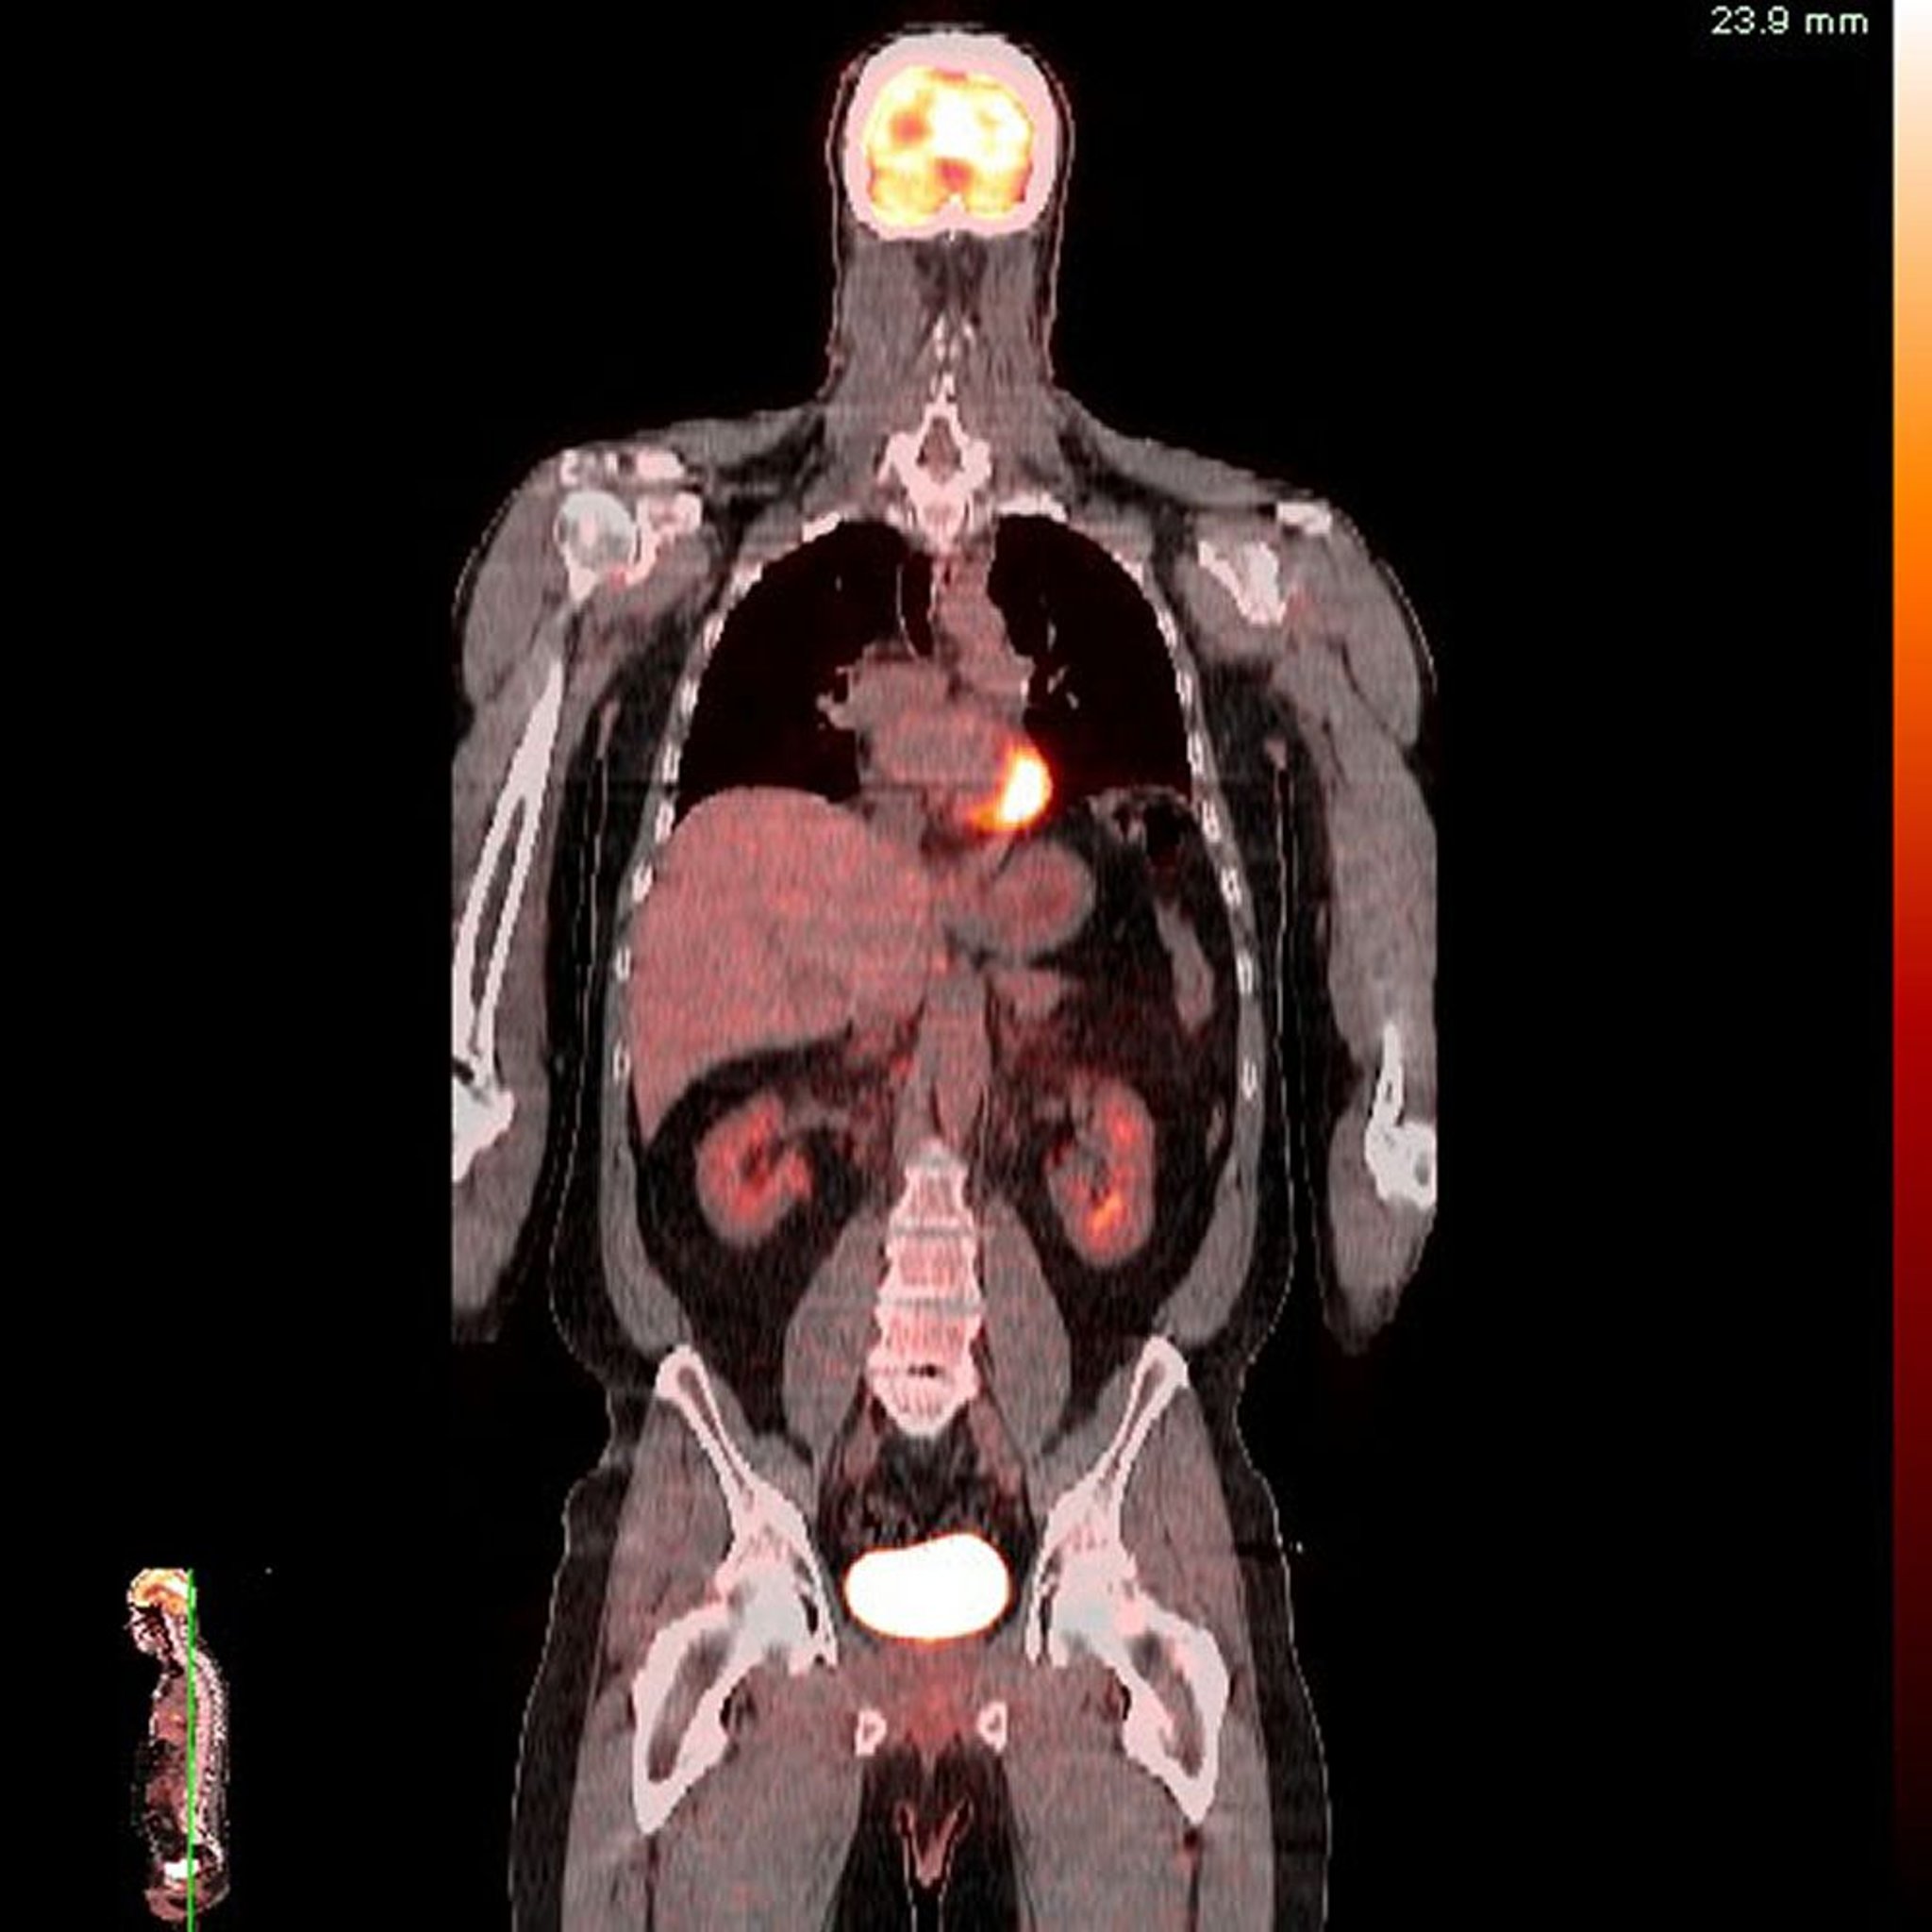

Positronen-Emissions-Tomografie/Computertomografie (PET-CT)

Bild von Dr. med. Jon A. Jacobson.

Positronen-Emissions-Tomographie (PET)